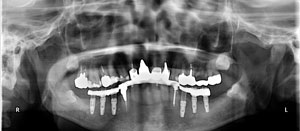

@@R.S‚³‚ñ@56Î —«  ‘åŠw‹³Žö @Žèp“ú@‚Q‚O‚O‚W”N ‚QŒŽ ‚X“úi“yj@㉺Š{  ƒm[ƒxƒ‹ƒKƒCƒhŽg—p@Ö¬“à’ÁÖ@•¹—p@@@

@@@@@ãŠ{  All on ‚U@‘¦Žž‰Ád@@

@@@@@@@@@@@@@ Rpl Tapered Rp  ‚P‚O mm(‚U–{)

@@@@@‰ºŠ{¶‰E@‘¦Žž‰Ád@ ‚R Unit Bridge@

@@@@@@@@@@@ @Rpl Tapered Rp  ‚P‚O mm(‚S–{)@@–ƒWƒ‹ƒRƒjƒAƒNƒ‰ƒEƒ“‚ÅÅI•â’Ô